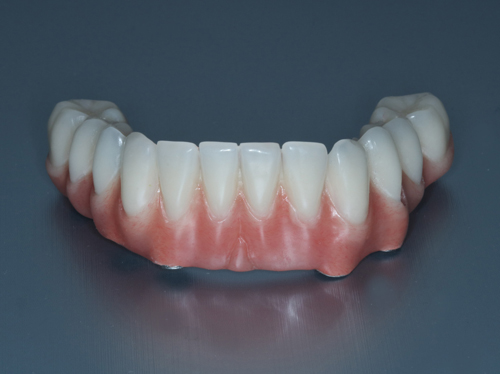

Se optó por colocar 5 nuevos implantes al mismo tiempo que se regeneraba su mandíbula con un injerto óseo. Se utilizaron 4 de estos implantes para ponerle una prótesis fija provisional al cabo de 24 horas (carga inmediata).

La cirugía se realizó bajo sedación consciente intravenosa por un médico anestesista, y fue muy cómoda para Joaquín, tal y como él nos cuenta. Tres meses después la prótesis provisional se cambió por una prótesis definitiva reforzada y más extensa al estar soportada esta por 6 implantes dentales.